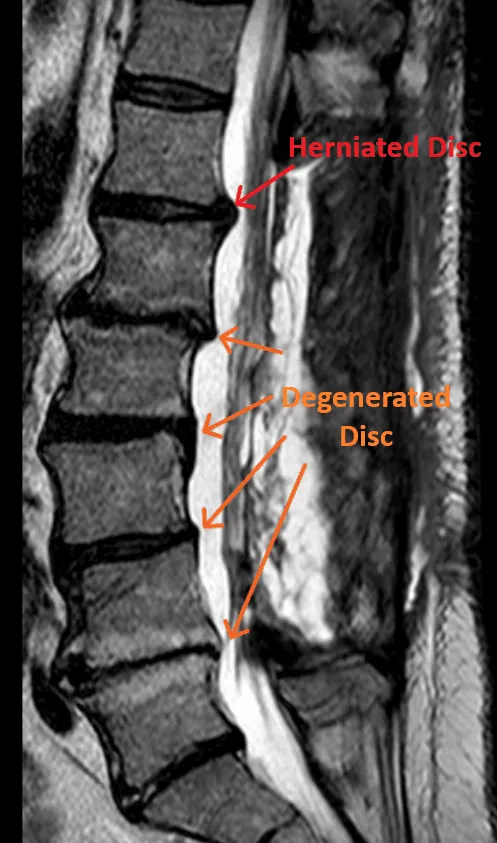

MRI scan of a spine showing labeled herniated and degenerated discs.

5) Disc Injuries Left Untreated

Disc herniations and degenerated discs are not treated when a laminectomy is performed. They are the most common cause of back and leg pain.